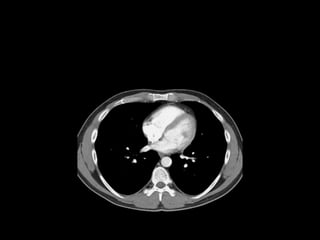

The document discusses the anatomy of the chest x-ray and CT scan by describing the lobes of the lungs and their locations. It also mentions the heart, mediastinum, hilum, and ribs. Several axial, coronal, and sagittal CT images are included with labels pointing out structures like the trachea, bronchi, lobes of the lungs, and fissures. In summary, the document provides an overview of lung and chest anatomy as seen on x-rays and CT scans through text descriptions and labeled medical images.